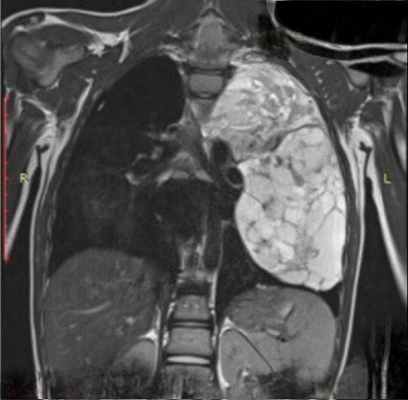

Ганглионеврома – доброкачественная опухоль из симпатических нервов. Возникает чаще всего в детском и юношеском возрасте, несколько чаще у женщин. Наиболее частой локализацией являются: заднее средостение, забрюшинное пространство, малый таз, надпочечники. В заднем средостении опухоли преимущественно располагаются в верхнем этаже, имеют одност ороннюю локализацию. При дорсальной локализации опухоль может прон икать в позвоночный канал, вызывая компрессионный паралич. Макроскоп ически опухоль имеет вид инкапсулированного узла диаметром от 3 до 10 см, бело-желтого цвета на разрезе. Как правило, наблюдаются единичные опухоли, однако описаны случаи множественных изолированных один от другого узлов ганглионевромы в сочетании с болезнью Реклингхаузена. Ганглионеврома при радикальном удалении редко рецидивирует , однако может малигнизироваться.

Учитывая крайнюю редкость этой опухоли, приводим наблюдение ганглионевромы из нашей практики.

Больной С., 21 год, поступил в отделение торакальной хирургии 301-го ОВКГ по поводу новообразования верхнего и переднего средостения. Опухоль средостения выявлена при ФОГК. При поступлении в 301-й ОВКГ больной жаловался на периодические боли за грудиной слева, иррадиирующие в левую руку. При КТ: «признаки объемного образования заднего верхнего средостения размерами 7,6×6,4×4,0 см, вероятнее всего невринома». 21.01.2010 г., интраоперационно: «опухолевидное образование в верхнем и заднем средостении, размерами 7,8×6,0×5,0 см, вдается в левую плевральную полость с продолжением до дуги аорты, отделено от костальной плевры, сосудов, органов средостения, ножка опухоли уходит вверх по позвоночнику на боковую поверхность шеи». При экспресс-биопсии исследован кусочек ткани опухоли размерами 4,0×2,5×0,7 см, мягкоэластической консистенции, желтоватого цвета. Микроскопически: при исследовании свежезамороженных срезов выявлена «опухоль в соединительнотканной капсуле, состоящая из клеток типа ганглиозных – крупных, со светлой зернистой цитоплазмой и крупными ядрами, расположенных поодиночке и группами, окруженных пучками соединительной ткани с фиброцитами, местами встречаются клетки с интенсивно окрашенными ядрами типа симпатобластов. Заключение: доброкачественная опухоль из симпатических ганглиев, наиболее вероятна – ганглионеврома». Дальнейшее исследование операционного материала: «Образование размерами 7,0×5,0×3,5 см, с гладкой поверхностью, покрытой капсулой, на разрезах ткань мягкоэластической консистенции, белесоватого цвета, дольчатая. Гистологически: опухоль представлена ганглиозными клетками, заключенными в фиброзную отечную строму, волокнистые структуры окрасились по Ван-Гизону в желтый цвет, местами отмечались ритмичные структуры, завихрения, участки миксоматоза, имелись группы мелких интенсивно окрашенных клеток типа симпатобластов; заключение: ганглионеврома».

Таким образом, вовремя диагностированная опухоль средостения позволила предупредить злокачественную трансформацию опухоли и избавила больного от неизбежного сдавления органов и структур средостения, а также поражения нервных стволов и спинного мозга. Возможность рецидива всех доброкачественных нейрогенных опухолей после их радикального удаления диктует необходимость наблюдения за этой группой больных в течение 5 лет после операции.